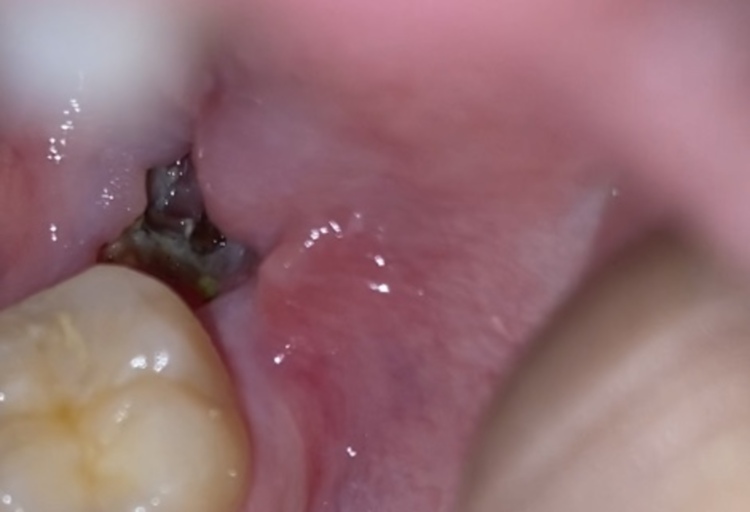

Wisdom tooth extraction - is this normal? (dry socket)

I had my wisdom tooth extracted 6 days ago and stitched up. 3 days ago, I noticed a very large hole in the gum where the site of extraction was. So far, I have not experienced any pain, soreness or tenderness. When shining a light on it, there is some yellow-ish stuff at the bottom of the socket. I have been doing warm salt water rinses to keep it clean. I wanted to know if this is normal or if it could be dry socket/infected. I also wanted to know if there was anything else I could do to help with healing.